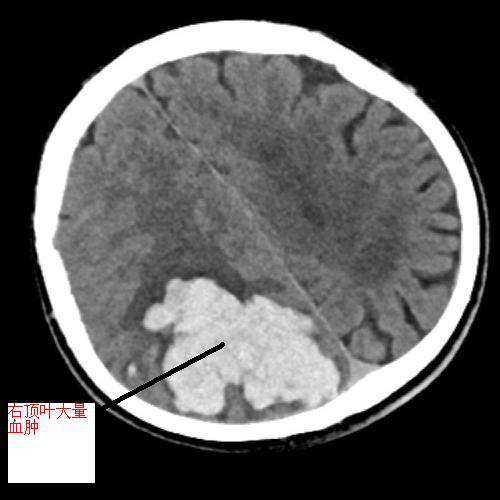

黃阿伯,現(xiàn)年60歲,9月中旬被發(fā)現(xiàn)躺于地上,言語(yǔ)不能、反應(yīng)遲鈍、左側(cè)肢體無(wú)力,緊急送至我院急診科,考慮右頂葉出血破入腦室,出血量超90ml,出血量大,周圍腦溝腦回、右側(cè)腦室受壓,呈嗜睡狀態(tài),有急診手術(shù)指征。不進(jìn)行手術(shù)后續(xù)水腫出現(xiàn)及加重、顱內(nèi)壓力增加、占位效應(yīng)加重,將進(jìn)一步損害腦組織。

▲左圖為術(shù)前顱內(nèi)血腫,右圖為手術(shù)后原血腫位置,血腫已基本清除